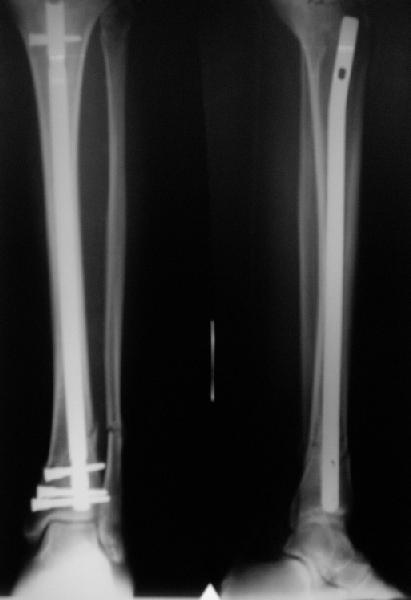

There are some more tricks which allow not to plate the fibula and provide good alignment and stability. A small wire distractor can provide alignment and restore length of both tibia and

fibula. Angular stability of the tibia is provided by insertion of more than two conventional medial-lateral locking screws. To maintain the position of the fibula perQ insertion of a single position screw often could be enough. I bet the articles didn't analyze the options.

A typical case is attached, also an image with intra-op reduction obtained by a small wire distractor, in the moment of insertion a Poller wire in AP direction. Fixation by a SIGN nail. Despite the fibula was not fixed healing was obtained with the unchanged alignment.

In delayed cases acute length restoration performed only in the tibia may leave the fibula shortened thus change the mortise. So it is reasonable to restore length of both bones simultaneously by distractor and fix the fibula not with open reduction and plating but just by a single perQ screw. Example attached.